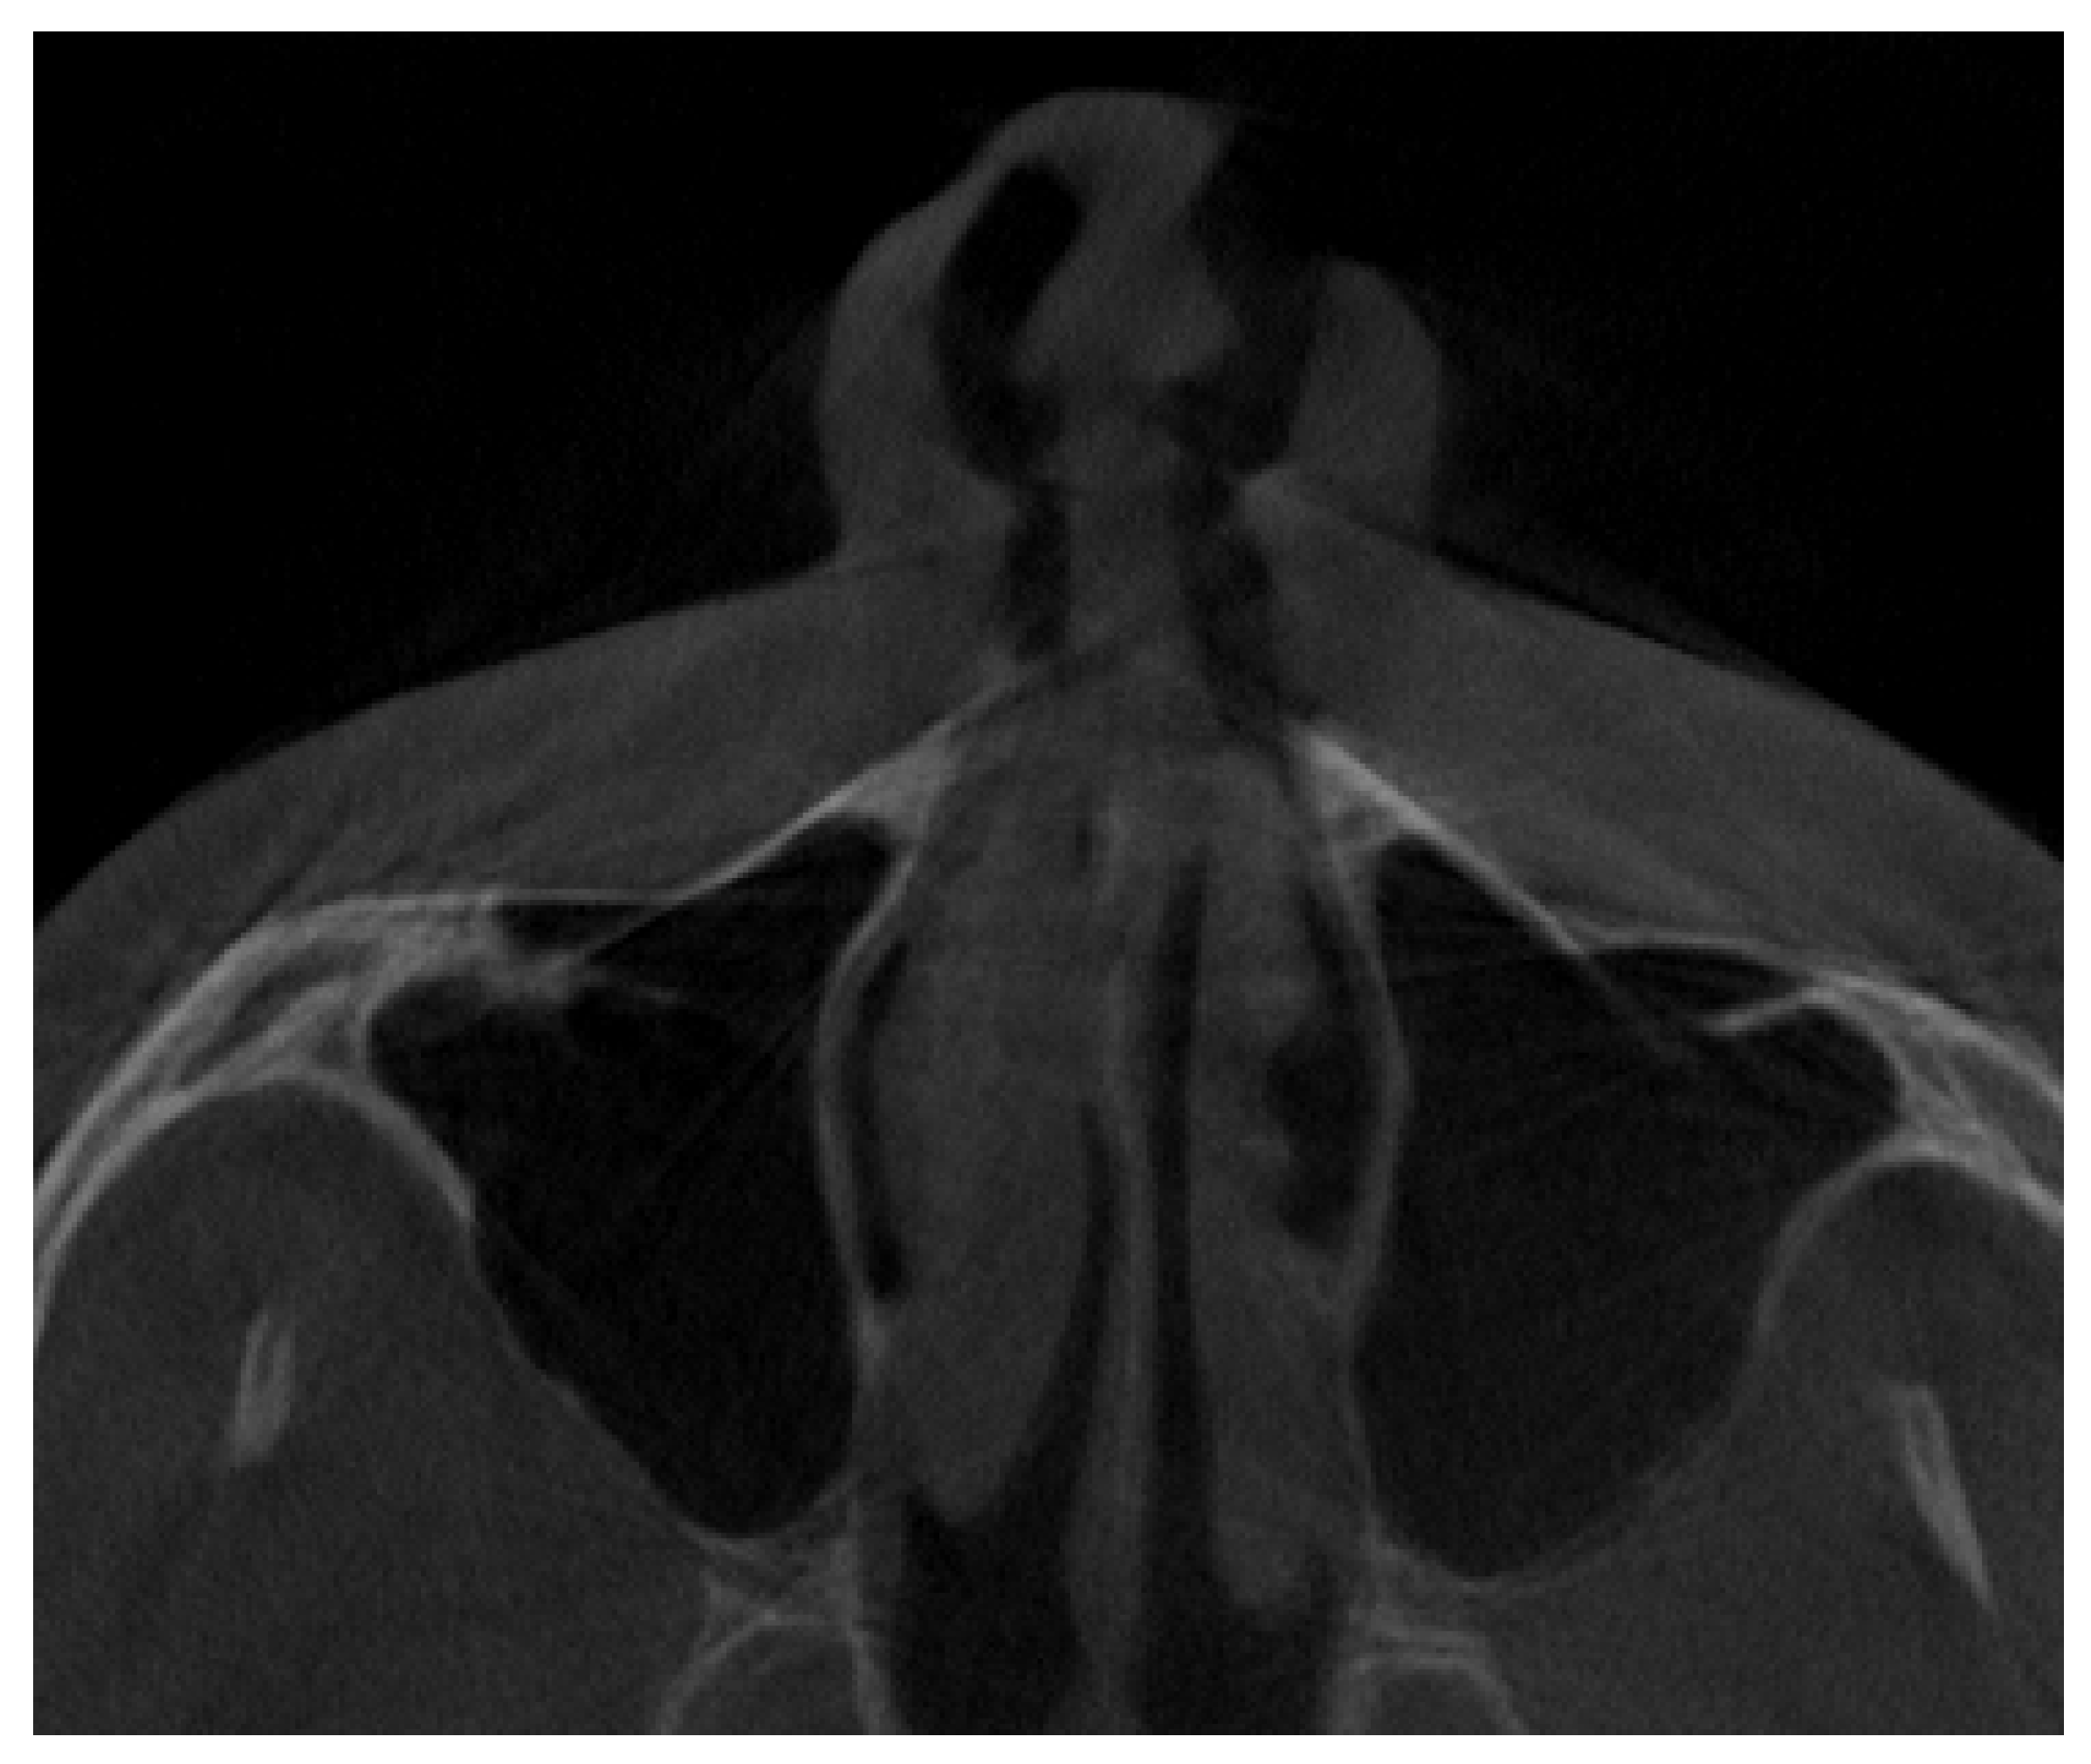

2.3. Methods—Classification Proposal

3.2. Classification Proposal